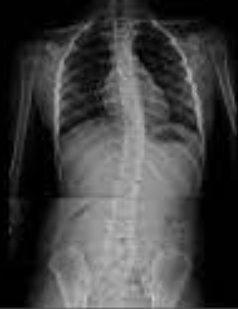

척추 측만증은 척추가 좌우로 휘어져 있는 상태를 말합니다. 정상적인 척추는 뒤에서 볼 때 직선을 이루어야 하지만,

척추 측만증이 있는 경우 척추가 'S' 형태나 'C' 형태로 휘어 있게 됩니다. 이로 인해 척추는 앞뒤로만이 아니라 좌우로도 굽어지게 되며, 이는 여러 가지 불편함과 건강 문제를 유발할 수 있습니다.

척추 측만증의 진단은 전문가에 의해 이루어지며, X-선 검사, MRI 등을 통해 척추의 휘어진 정도를 정확하게 평가합니다. 진단 과정에서 환자의 나이, 성장 상태, 척추의 휘어진 정도 등이 고려됩니다.